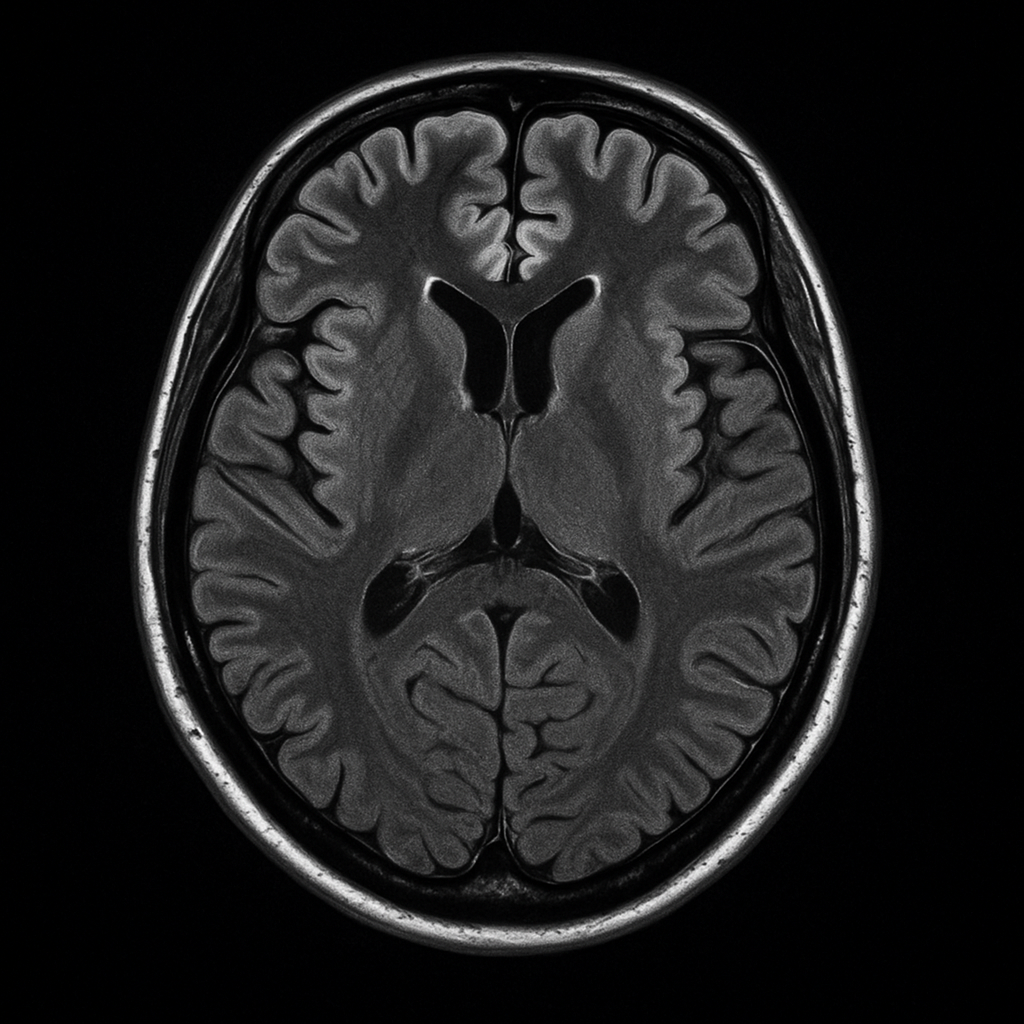

Imagem ilustrativa de uma ressonância magnética